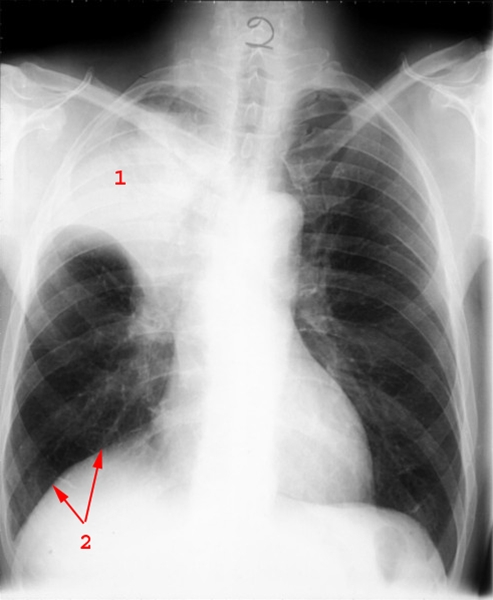

Småcellet anaplastisk carcinom, før behandling

Atelektase af højre overlap (1) på grund af tumor, som afklemmer overlapsbronchus.

1. Atelektase (sammenfald af lungevævet)

2. Eleveret højresidig diafragma pga. atelektasen og dermed følgende volumenformindskelse